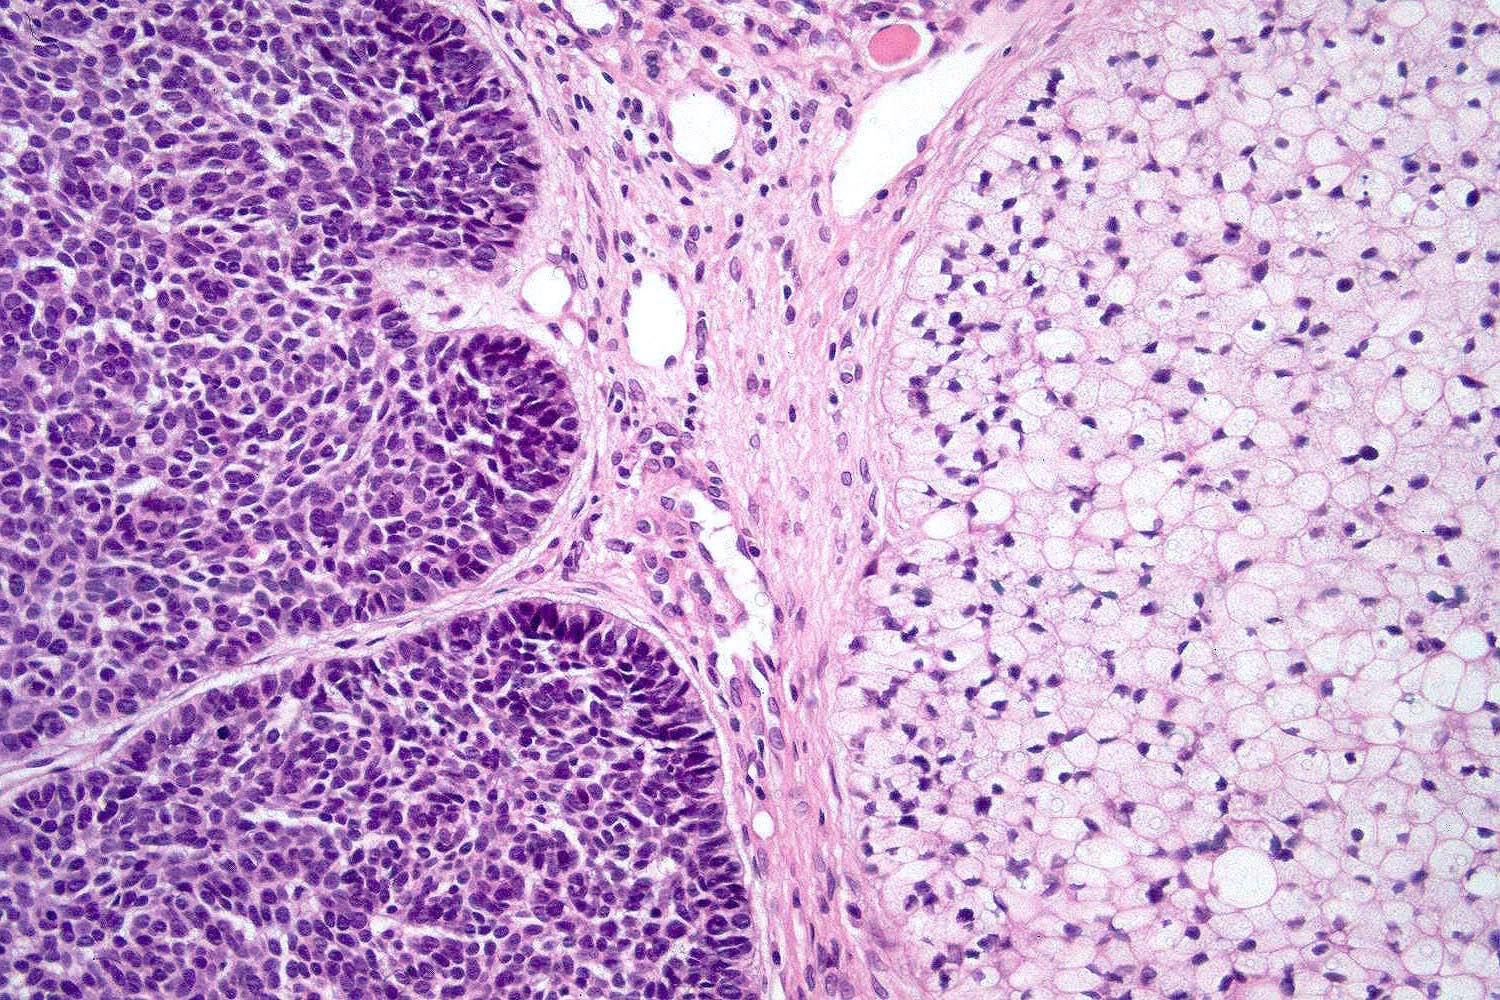

Common variants (Calonje: McKee's Pathology of the Skin, 5th Edition, 2019)

- Micronodular BCC

- Small basaloid nests

- Peripheral palisading less prominent

- Retraction artifact usually absent

- Can diffusely infiltrate the dermis and extend into the subcutis

- Superficial BCC

- Isolated basaloid lobules projecting from the lower margin of the epidermis

Microscopic (histologic) images

Contributed by Antonina Kalmykova, M.D., Phillip H. McKee, M.D., Sate Hamza, M.D., Eduardo Calonje, M.D.,

Wayne Grayson, M.B.Ch.B., Ph.D., James Sampson, M.B.B.S., M.Sc. and Assia Bassarova, M.D., Ph.D.